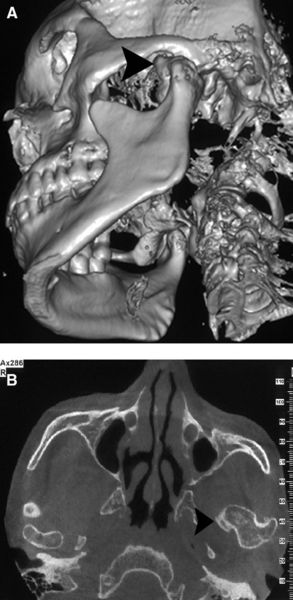

颞下颌关节髁突骨软骨瘤的发生部位(有图片)_颞下颌关节病_疾病介绍

图片尺寸1000x684

颞下颌关节髁突骨软骨瘤的发生部位有图片

图片尺寸293x600

颞下颌关节髁突骨软骨瘤的发生部位(有图片)

图片尺寸600x450